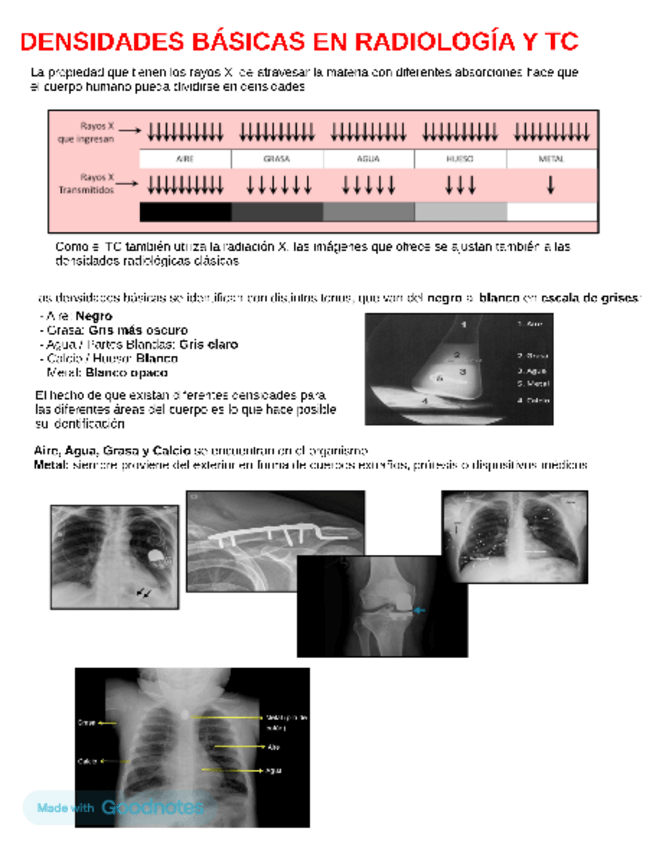

te habla sobre densidades básicas en radiologia, TC y RM, cortes axilares, sagitales, coronales y reconstrucciones tridimensionales en radiologia